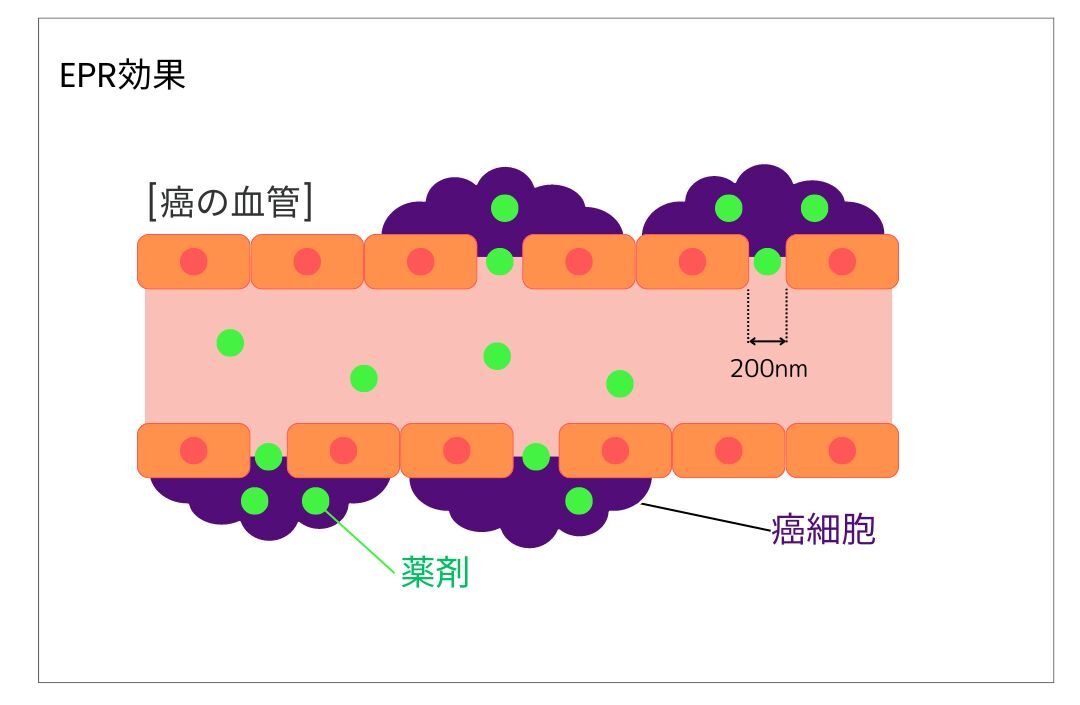

リポソーム化した薬剤を使用し、EPR効果によってがん細胞に薬剤を届けます(リポソーム化した薬剤とは、薬を小さなカプセルに包んでがん細胞に届ける技術であり、EPR効果とは、このカプセルががん細胞に集まりやすくなる効果のことです)。正常な細胞には影響を与えないため、副作用が少ないのが特徴です。

➁ 薬剤をがん細胞へ集積

正常な血管壁は整然としており緻密に構成されていますが、がん組織の血管壁はこれとは異なり、構造に乱れが見られます。この構造上の差異を利用して、薬剤を効率的にがん細胞に送り届けることができます。この方法は「EPR効果」として知られ、がん治療において重要な役割を果たしています。

これらの光感受性物質をリポソーム化(一般的に100nm程度の大きさ)し、EPR効果を利用する事で薬剤をがん細胞に集積させます。

がんの新生血管は不完全であり、新生血管内に約200nmの隙間が存在するのに対し、正常な細胞は6nm~7nm程度の隙間が存在します。

その為、約100nmのリポソーム化した薬剤は正常な細胞には取り込まれず、新生血管から腫瘍の組織内に運ばれ、蓄積します。

これらの血管壁差を利用し、癌細胞へ効率的に薬剤を運ぶ特性DDS(ドラッグデリバリーシステム)をEPR効果と呼びます。

この性質により、がん細胞へ選択的に薬剤を届けることができるため、正常細胞へのダメージが少ない利点があります。

ICGを使用した光免疫療法では、リポソーム化した薬剤をEPR効果を用いてがん細胞へ選択的に集積させ、特定の波長の光を当てることでがん細胞を攻撃します。

正常な血管壁は乱れなく緻密な状態ですが、がんの血管壁は塑像(そぞう)な状態となっています。 がん細胞は酸素を含む栄養を得て成長するために血管を新生させます。新生血管は正常血管と比較して不完全であり、 血管内皮細胞間に約200nmの隙間が存在しています(正常な細胞の場合6~7nm程度)。 その為、薬剤(数百nmのナノ粒子)は正常な血管には取り込まれずに、腫瘍の組織へ運ばれます。 この血管壁差を利用したドラッグデリバリーシステムをEPR効果(ノーベル賞候補の熊本大学名誉教授である前田浩博士による技術)といい、薬剤をがん細胞に定着し、 光を照射する事でがん細胞を攻撃します。